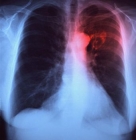

Pneumotórax é o acúmulo de AR no espaço pleural – o espaço entre o pulmão e as costelas. O pneumotórax pode ser causado por trauma (acidentes, perfurações etc), mas também pode ser espontâneo – uma pequena parte do pulmão “fura” ou “rasga” e os alvéolos que foram rompidos permitem o vazamento de ar.